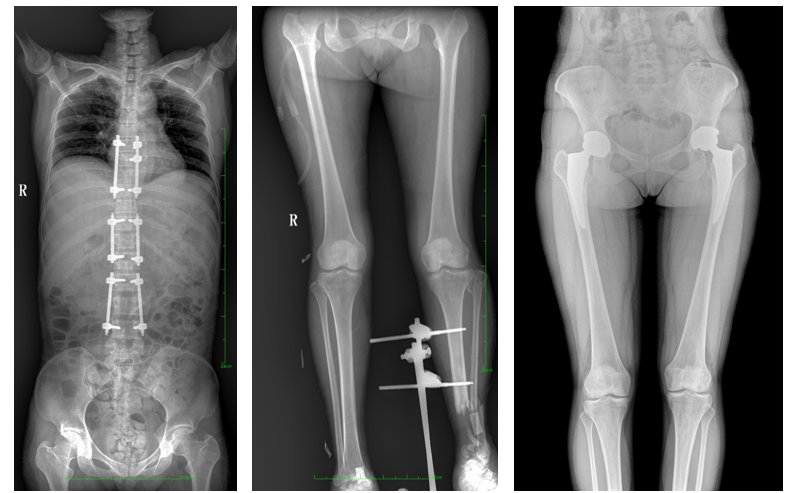

17"*34"有效視野,是市面大尺寸平板的2倍,一次成像不拼接。相較于多張攝影再軟件拼接的DR設(shè)備,PLX8600解決了拼接圖像存在密度不均勻,拼接處圖像配準(zhǔn)和放大效應(yīng)等問題,給臨床帶來了真正的大視野影像解決方案,高清畫質(zhì),準(zhǔn)確成像不失真,可一次性覆蓋全脊柱或雙下肢影像。PLX8600大視野平板動態(tài)DR攝影速度快,患者可以更快的完成檢查,且單次攝影輻射劑量是常規(guī)多張攝影再軟件拼接DR的1/2或1/3,低劑量給患者更多關(guān)愛。

除常規(guī)靜態(tài)攝影外,PLX8600大平板具備動態(tài)透視和點片功能,透視采集功能可支持大視野、多角度的可視化觀察。通過可視化的動態(tài)影像,配合點片功能,能夠很好的觀察復(fù)雜部位病灶,有效的抓取關(guān)鍵幀,降低患者多次攝片的概率,安全又高效。如:全脊柱狀態(tài)評估、長骨關(guān)節(jié)活動度、下肢靜脈造影瓣膜功能評估、消化道功能評估、脊髓造影等更多大視野臨床應(yīng)用,多面手給醫(yī)生更多驚喜。